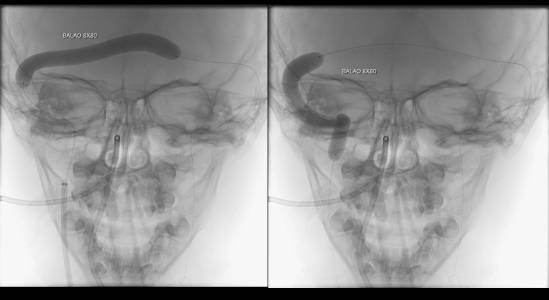

Foi realizada discussão entre as diversas especialidades, em vista da não melhora com o uso do anticoagulante, foi sugerido a tentativa de trombectomia mecânica do seio dural.

O caso clínico apresenta a utilização de materiais com finalidades primárias para trombectomia mecânica no contexto de acidente vascular cerebral (Rebar 27 + Solitaire) e o balão Copernic RC (Balt) comumente utilizado auxiliando na embolização de fístulas durais para os seios, auxiliando no processo de trombectomia mecânica no contexto de extensa trombose venosa cerebral.